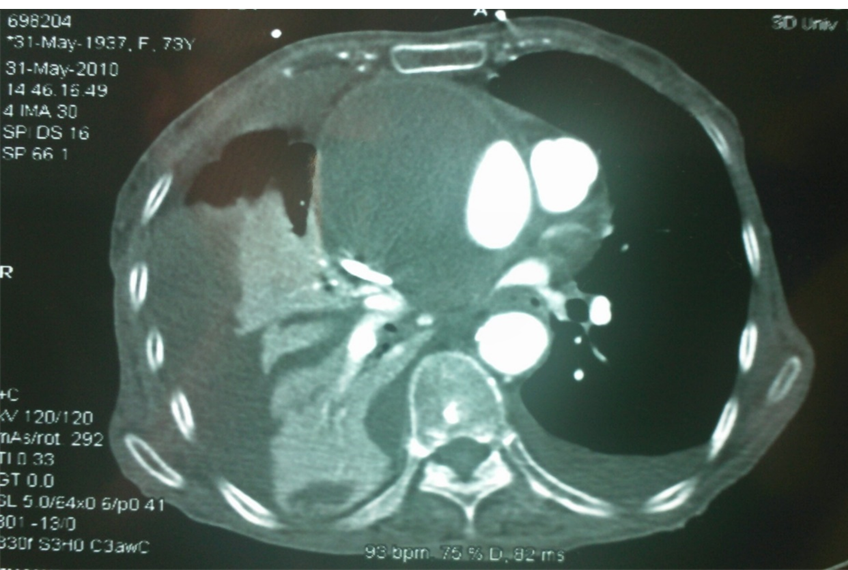

我们早期曾遇到一例升主动脉夹层治疗失败的病例(因失败未留存完整影像),但事后复盘发现,根本原因在于对主动脉三维解剖认知不足。当时采用预开窗技术,支架释放后发生近端移位和远端扭转,导致左颈总动脉与头臂干被遮蔽,最终需紧急补救性支架+两次搭桥手术。

全麻下双上肢穿刺,右股动脉切开,左上肢路径造影,右上肢进保护性导丝,对支架预开窗后植入升主,因破口较大,支架近端掉入破口,远端扭转遮蔽左颈总动脉及头臂干,窗口对破口,再次植入一枚38-80支架,封住近端破口后,以8*60支架开放右侧头臂干,6*10人工血管行右锁骨下-左颈总搭桥,取颈前静脉行左椎动脉-人工血管搭桥,之后造影,头臂动脉均通常,术后约2小时患者清醒。